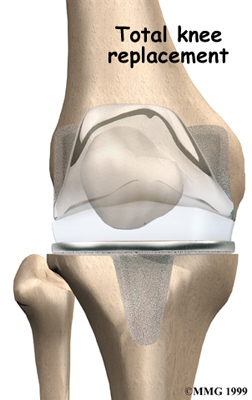

Artificial Knee Replacement

An artificial knee replacement is the ultimate solution for advanced knee OA.

Surgeons prefer not to put a new knee joint in patients younger than 60. This is because younger patients are generally more active and might put too much stress on the joint, causing it to loosen or even crack. A revision surgery to replace a damaged prosthesis is harder to do, has more possible complications, and is usually less successful than a first-time joint replacement surgery.

Related Document: FYZICAL Grantsburg's Guide to Artificial Joint Replacement of the Knee